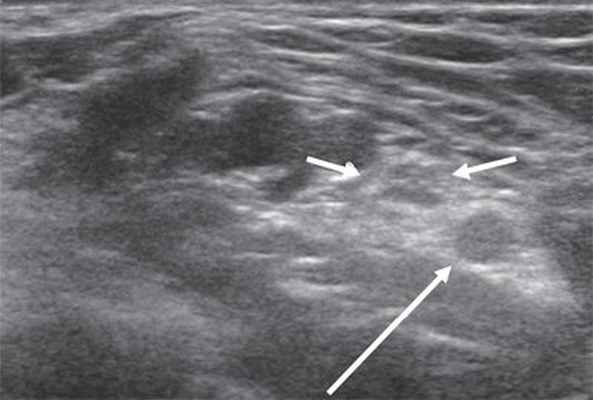

Срединный нерв формируется из латерального и медиального пучков плечевого сплетения. На плече n. medianus располагается в медиальной бороздке двуглавой мышцы кпереди от плечевой артерии. Срединный нерв является самым крупным нервом верхней конечности, поэтому его визуализация не представляет сложностей, однако легче всего можно получить ультразвуковое изображение нерва в области карпального канала, где он расположен поверхностно, а также на уровне локтевого сустава. В последнем случае в качестве маркера целесообразно использовать сосудистый пучок. В области локтевого сустава срединный нерв располагается медиальнее по отношению к более глубоко расположенным плечевой артерии и вене (рис. 3).

Рис. 3. Срединный нерв на уровне локтевого сустава в поперечной проекции (короткие стрелки). Рядом визуализируется плечевая артерия (длинная стрелка).